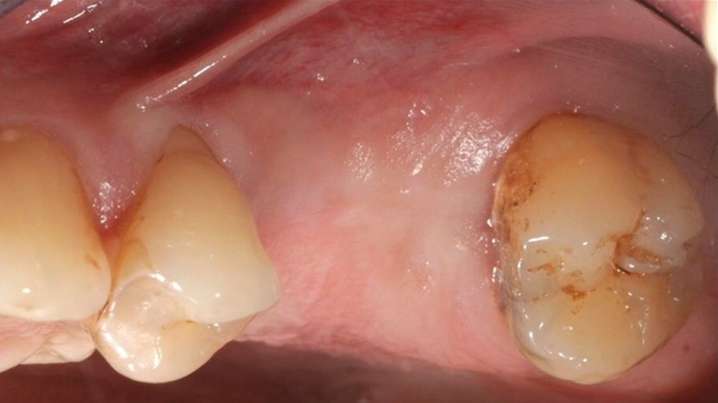

Clinical case: Delayed implant placement: sinus floor elevation by means of lateral

approach & implant placement with GBR

- Courtesy of Dr. Irfan Abas, Netherlands -